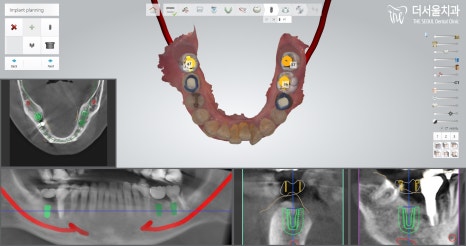

문정동치과 에서 컴퓨터 분석 프로그램으로

먼저 시뮬레이션을 돌린 뒤,

픽스처를 심으면 거의 알맞은 위치에

잘 심어지는 것을 확인할 수 있었습니다.

그렇기에 최소 내원 및 최소 절개로

수술이 진행되고 있으니

크게 통증이 없다는 얘기를 하는 것이겠죠?